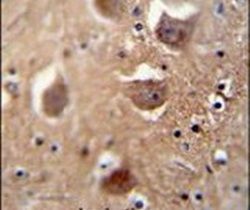

Supportive validation

- Submitted by

- Invitrogen Antibodies (provider)

- Main image

- Experimental details

- Immunohistochemistry analysis in formalin-fixed, paraffin-embedded human brain tissue using a TDRD7 polyclonal antibody (Product # PA5-24462), followed by HRP-conjugated secondary antibody and DAB staining.